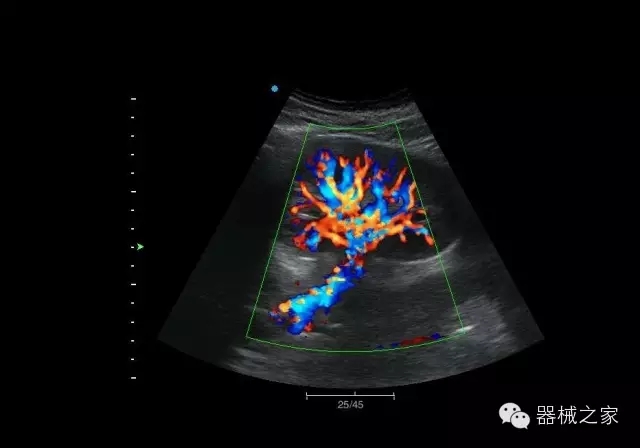

臨床圖片賞析

結甲

腎臟血流

肝血管瘤